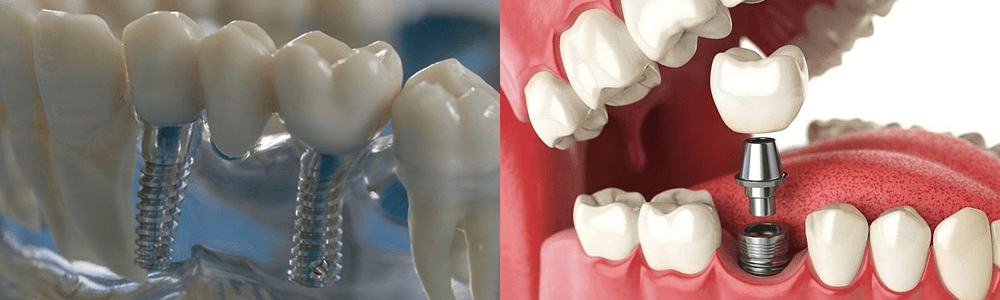

Современные коронки на зубные импланты: виды и фото-примеры